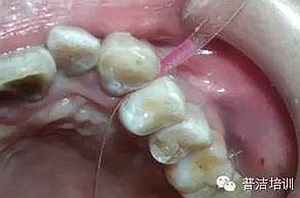

粘結(jié)完成后